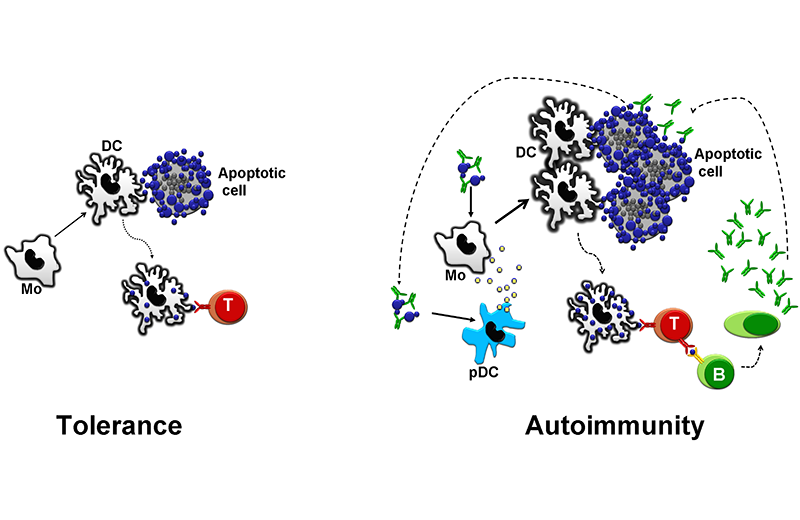

En personas sanas, el material de cĂŠlulas apoptĂłticas se presenta a cĂŠlulas T en un contexto no inflamatorio. Esto contribuye a mantener inactivas las cĂŠlulas T autoreactivas (izquierda). En pacientes con lupus eritematoso generalizado (LEG), una serie de factores que incluyen baja afinidad de receptores Fc, baja densidad de receptores de complemento y deficiencias genĂŠticas o adquiridas de componentes del complemento disminuyen la capacidad del sistema de depurar complejos inmunes y material apoptĂłtico. Esto causa una sobrecarga de autoantĂgenos que, en personas susceptibles, conlleva al desarrollo de autoanticuerpos. Los autoanticuerpos opsonizan cĂŠlulas apoptĂłticas lo que favorece un contexto inflamatorio de presentaciĂłn antigĂŠnica, creando asĂ un cĂrculo vicioso.